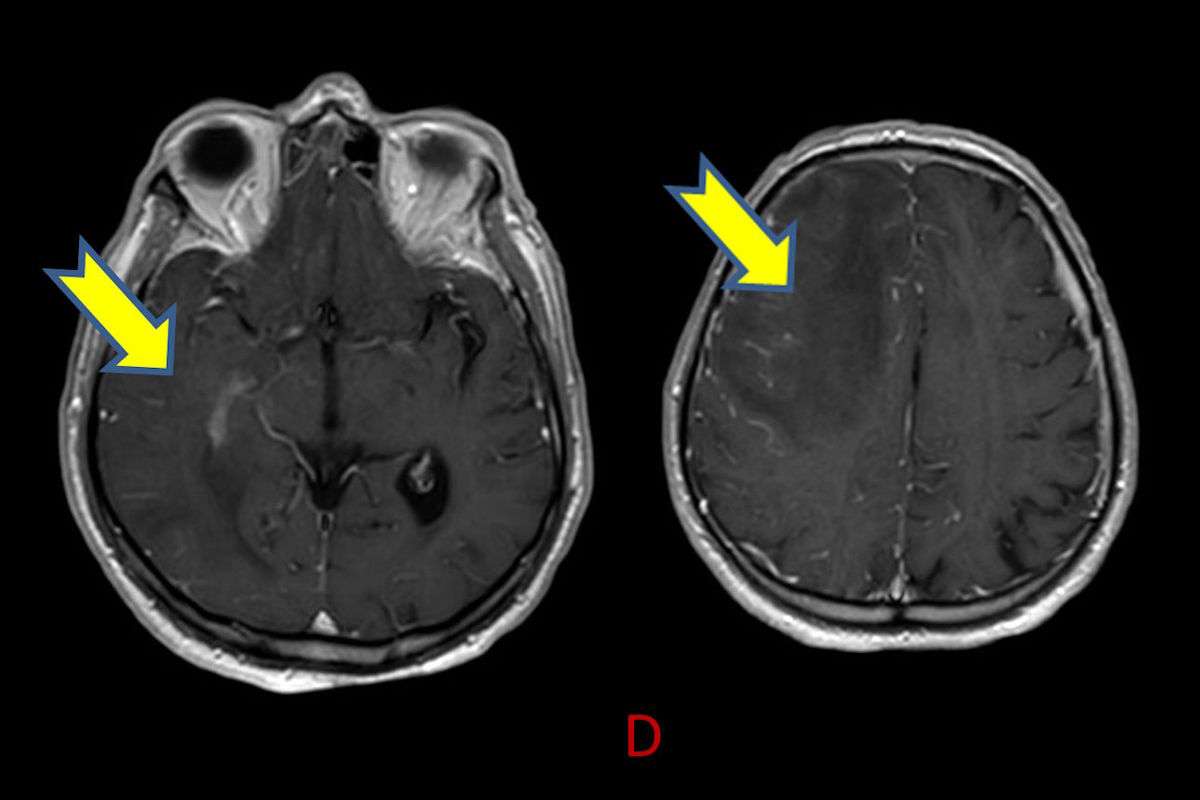

- D) Kontrastlı T1A sekansta hafif leptomeningeal boyanma (sarı ok).